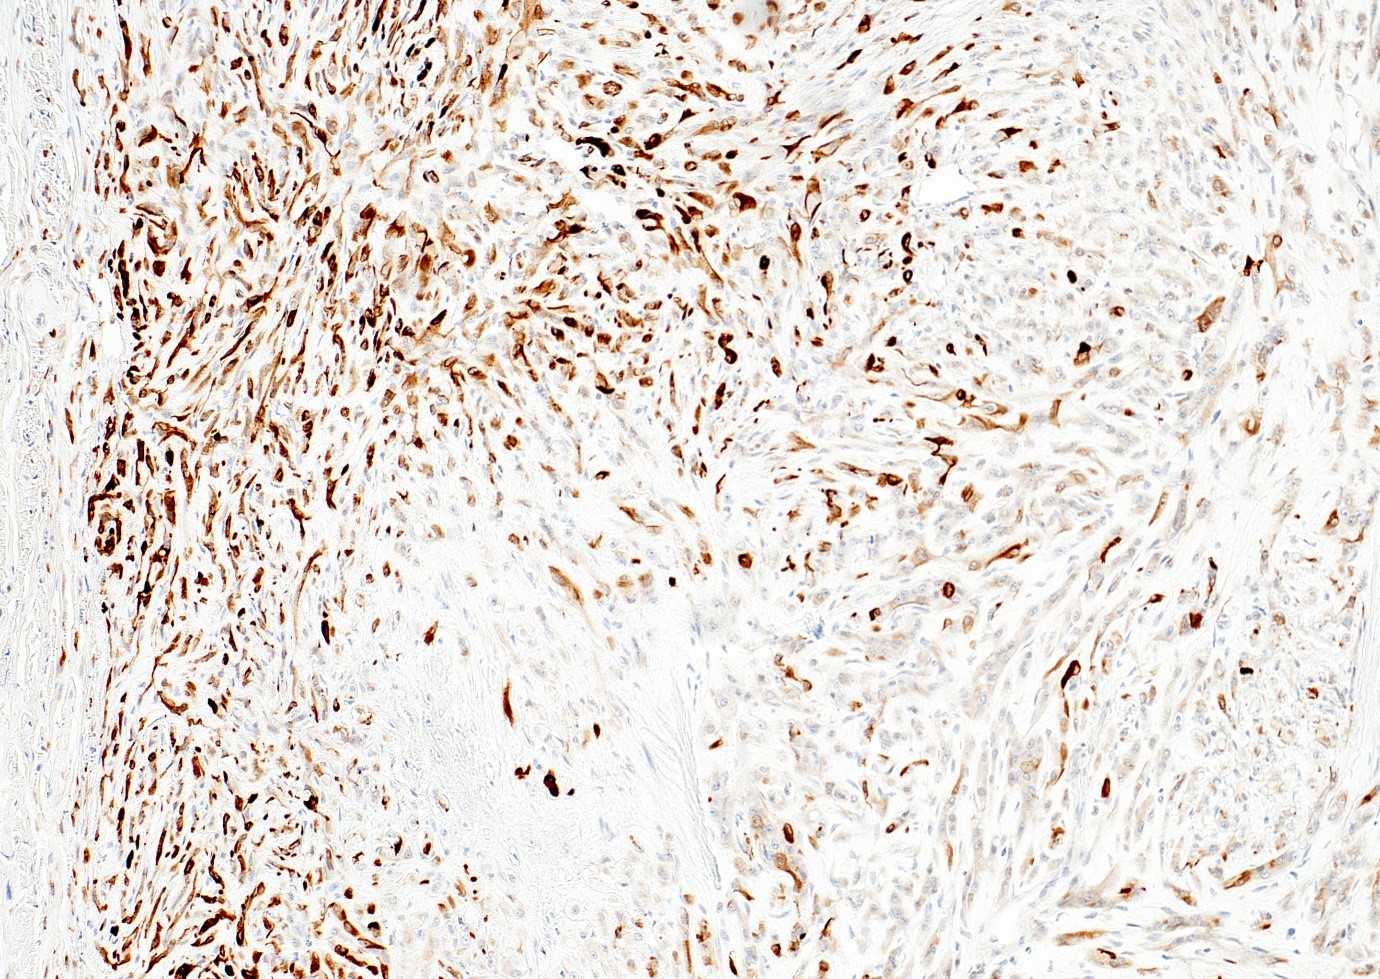

Microscopic (histologic) images

- WWTR1-CAMTA1 subtype (classic EHE):

- Cords, strands or small nests of large endothelial cells with abundant eosinophilic cytoplasm embedded in a myxohyaline stroma

- Tumor cells have vesicular, round to oval, sometimes indented nuclei

- Some tumor cells have intracytoplasmic, round, clear vacuoles representing small vascular lumina, which may contain erythrocytes

- Up to 10% of cases exhibit frank malignant features of prominent nuclear pleomorphism, increased mitotic activity, solid growth or necrosis; these tumors resemble epithelioid angiosarcoma and have a more aggressive behavior (Am J Surg Pathol 2008;32:924)

- ERG, CD31, CD34 (can be negative), podoplanin (D2-40), FLI1, von Willebrand factor (Diagn Pathol 2014;9:131, Am J Surg Pathol 1997;21:363)

- CAMTA1 in WWTR1-CAMTA1 rearranged tumors (Am J Surg Pathol 2016;40:94)